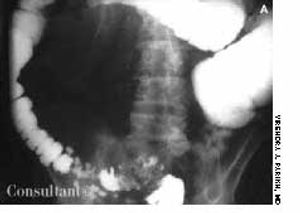

For 2 months, a 73-year-old man had experienced dysuria, pneumaturia, and foul-smelling urine. He had an attack of diverticulitis a year earlier. At that time, he underwent a barium enema study, which showed multiple sigmoid colonic diverticula with spasm.

A 73-year-old man with chronic constipation presented to the emergency department with hematochezia. Mild, colicky abdominal pain had begun 3 days earlier; obstipation had been present for 10 days.The patient’s history included a cerebrovascular accident 2 years earlier and Parkinson disease; he was taking anticholinergic drugs.